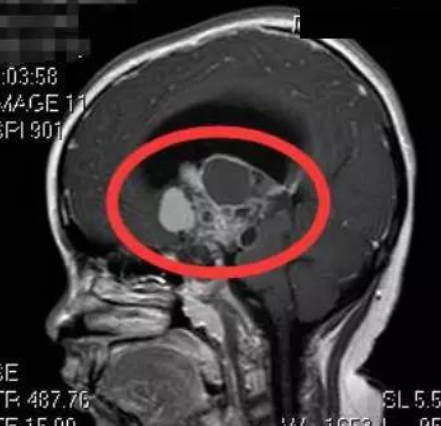

Nana,今年10岁,但是已经看不见这个国际了。那是2014年12月,在几周的时间里,她的视力迅速恶化。她在家里附近的医院接受了核磁共振检查,结果显示肿...

颅咽管瘤是由鞍区或鞍上区Rathke囊的残余细胞形成的肿瘤,具有囊性和实型成分。虽然它们是良性的,WHO为I级,但由于该病难以治愈,使得它们的生长行为...

早在20世纪90年代,哈维·库欣(Harvey Cushing)就将颅咽管瘤称为“较可怕的颅内肿瘤”,因其病情复杂、被发现时肿瘤往往已经生长较大,不同的发病部位...

什么是颅咽管瘤?INC国际神经外科指出,颅咽管瘤是起源于上皮细胞的良性肿瘤,约有半数发生于儿童和青少年,为发病一高峰期,成年人多见于40-60岁,...

颅咽管瘤占儿童脑肿瘤的 5% 到 15%,成人占 1%。脑垂体区域容易发生颅咽管瘤,可能影响内分泌功能。此外,它们靠近视神经和视交叉可能会导致视力问题...